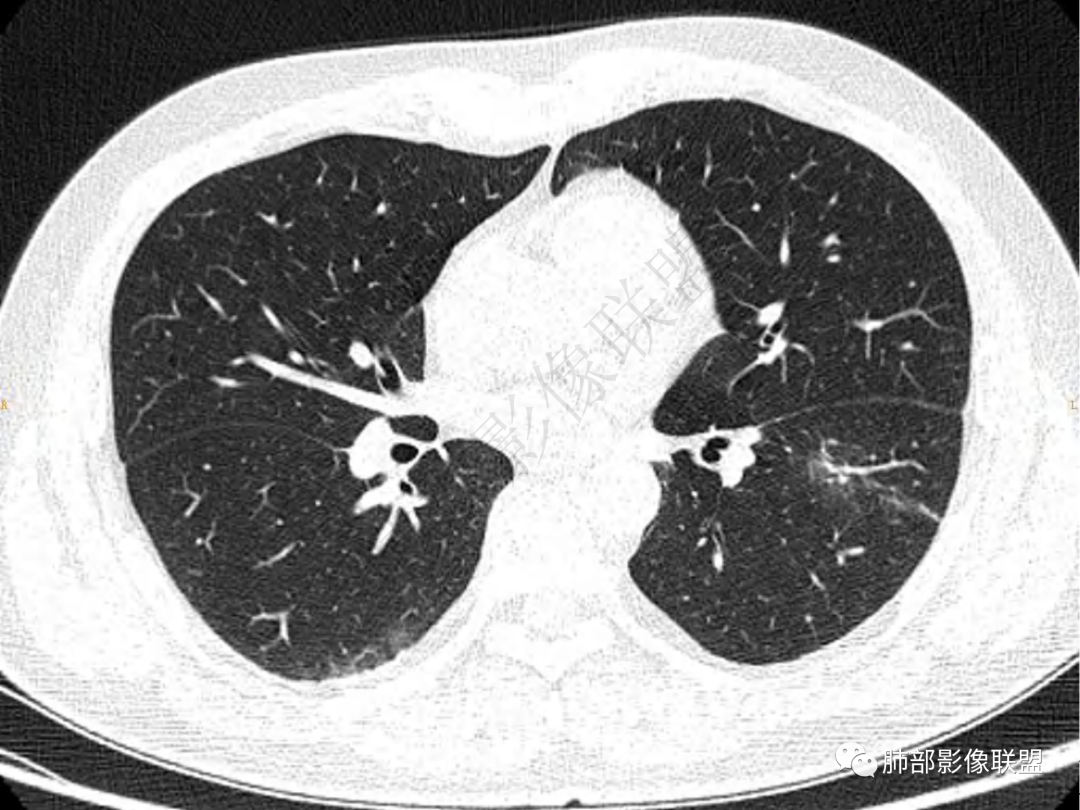

2.左肺下叶团片影,跨背段及内前基底段,实性部分类椭圆形,密度不甚均匀,可见毛刺及棘状突起,未见典型分叶及胸膜凹陷。病灶上下缘可见相应肺段支气管旁进侧出,管壁轻度增厚,未见狭窄阻塞。

3.周边较大范围磨玻璃影,边界相当模糊,小叶增厚明显。注意叶裂另一侧、左肺舌段亦可见磨玻璃影及增厚的小叶间隔。未见明确卫星病灶。

4.实性部分不均匀环形强化并显示一小范围低密度坏死区或空洞。较之肺窗,整体纵隔窗范围较小,提示病灶并不十分密实。抑或为不同时段图像。